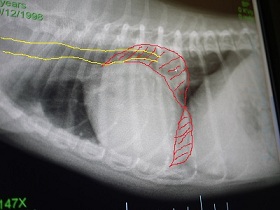

上↑の写真と全く同じなんですけど・・

今迄、レントゲンを見せてもらってても、

白くハッキリと確認できる部分だけが心臓なんだと思ってたらね

赤く色付けした部分は肥大してしまってるところだよ。って教えてもらってね。

(ちょっと大袈裟に書きすぎたかも^^; )

黄色は気道です。

・・そりゃ。咳・・出るわぁ・・(T▽T;)

気道を圧迫どころか、重なるように押し上げてる状態だものね・・。

レントゲン1枚にしても 何って分かりやすいんでしょう・・。